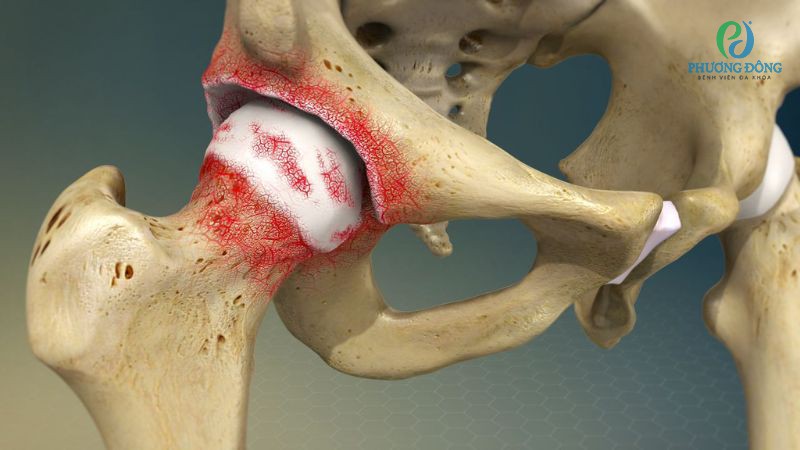

Viêm khớp, hay cụ thể hơn là viêm khớp háng, là nguyên nhân hàng đầu khiến vùng hông bị đau nhức. Bệnh xảy ra do lớp sụn bảo vệ khớp bị bào mòn, khiến các đầu xương ma sát trực tiếp với nhau, gây ra cảm giác đau nhức âm ỉ, cứng khớp và khó khăn khi vận động.

Viêm khớp háng là nguyên nhân hàng đầu khiến hông bị đau nhức

Thoái hóa khớp háng

Thoái hóa khớp háng là kết quả của quá trình lão hóa tự nhiên của cơ thể con người, thường ảnh hưởng đến khả năng vận động và chất lượng cuộc sống của người trên 50 tuổi. Cơn đau có xu hướng tăng lên khi đứng lâu, di chuyển nhiều hoặc vận động mạnh.